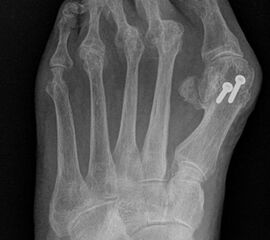

Die Operation nach Hoffmann-Tillmann ist in der Rheumaorthopädie ein schon seit Jahrzehnten genutztes Verfahren, um bei destruierten Metatarsale Köpfen und luxierten, nicht mehr reponiblen Zehen in den Grundgelenken, die Patienten wieder gehfähig zu machen und die Schuhversorgung zu erleichtern.

Es handelt sich bei dem „rheumatischen Vorfuß“ nicht um eine „normale“, meist rein mechanische Metatarsalgie, sondern um eine durch Synovialitiden sich häufig schnell entwickelnde und sehr ausgeprägte komplexe Fehlstellung. Die persistierend chronische Entzündung mit hoher Aktivität führt zu einer Veränderung oder Verlust der Sehnenfunktion mit Ruptur der plantaren Platte und Ligamente, subchondralen Usuren, Knorpel- und Knochendeformationen. (siehe auch Kapitel "Die Stainsby OP" von Briggs P, Stainsby D - Abschnitt "Pathomechanik des deformierten Rheumafußes").

Durch die verbesserte medikamentöse Rheumatherapie sind diese ausgeprägten Knochendestruktionen rückläufig. Die Indikation zur Resektionsarthroplastik mit Entfernung der Metatarsale II-V Köpfchen wird damit seltener 56. Auch bei nur teilweise erhaltenen Gelenken sollte in der modernen Rheumafußchirurgie einem gelenkerhaltenen Verfahren der Vorzug gewährt werden, da der Gelenkerhalt mit besseren funktionellen Ergebnissen korreliert 7. Allerdings werden auch noch heute schwere Gelenkdestruktionen beobachtet, da ein Teil der Patienten auf die medikamentöse Therapie unzureichend anspricht oder die Therapien nicht wahrnimmt.

Die Resektion der Metatarsaleköpfe ist dann indiziert, wenn bei Destruktion der Metatarsophalangealgelenke (LDE IV und V - siehe Tabelle 1) keine gelenkerhaltenden Alternativen zur Verfügung stehen.